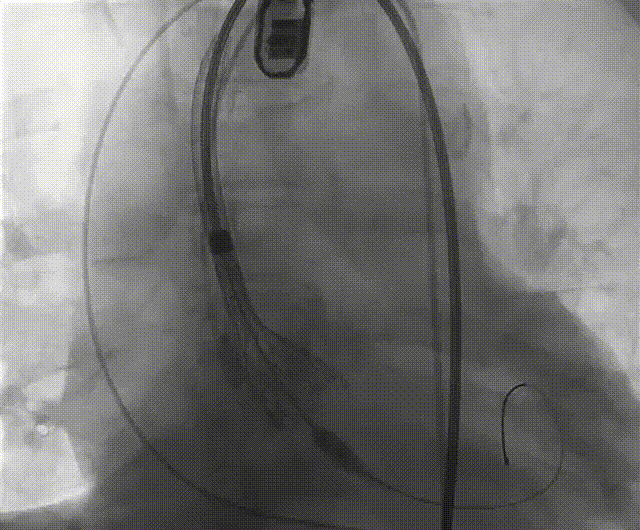

根部造影

左冠脉提前植入延长导管,预埋冠脉导丝。

20mm球囊预扩张,无腰征,无造影剂泄露。

vitaflow tav24瓣膜轻松过弓初始定位瓣环0位开始释放,班第一次释放瓣膜在转移到瓣上,综合决定回收采取第二次瓣膜释放。

第二次精准零位释放,决定完全释放。

释放后多体位观察造影,瓣膜位置良好,展开良好,轻微瓣周漏。